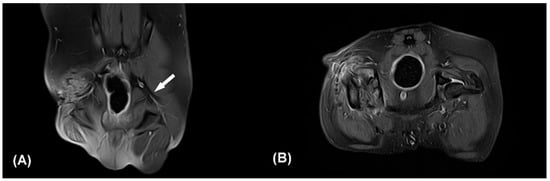

Figure 2. Contrast enhanced fat-suppressed proton density weight images (CE-FS-PDWI) of dorsal (A) and transverse plane (B). The white arrow indicates the intact left sciatic nerve (A). The right sciatic nerve strand is not clearly identifiable (A,B). Note that focal discontinuity of the sciatic nerve, muscle fibrosis, and edema of surrounding soft tissue. Q: quadriceps muscle, Bi: biceps femoris muscle.

Based on the patient’s clinical signs, history, and the results of physical and neurological examinations, iatrogenic right-sided sciatic neuropathy was suspected since the neurological deficit was shown immediately after the previous operation and the skin incision was caudal to the greater trochanter where the sciatic nerve was located. The patient was sedated with intramuscular administration of medetomidine (30 μg/kg). Radiographic examination including ventrodorsal hip extended and lateral view of the pelvis and craniocaudal and open-leg mediolateral view was performed for the right coxofemoral joint. Despite of previous FHNO surgery, irregular bony proliferations around the osteotomy line and acetabular rim were identified on radiographs. Magnetic resonance imaging performed under general anesthesia revealed inconspicuous continuity of the right sciatic nerve at the greater trochanter level (Figure 2). In the transverse and dorsal planes, hypointense structures appearing as osteophytes were observed in the right greater and lesser trochanters and acetabulum on T1 and T2-weighted (W) and contrast enhanced fat-suppressed proton density weight images (CE-FS-PDWI). On T1W and T2W images, peripheral muscles were observed to be non-uniform in intensity due to fibrotic changes. Volumes of the right adductor, gluteal, quadriceps, biceps femoris, semitendinosus, and semimembranosus muscles were decreased compared with the left side, and fatty infiltration was present. These findings were consistent with sciatic nerve injury and muscle atrophy.